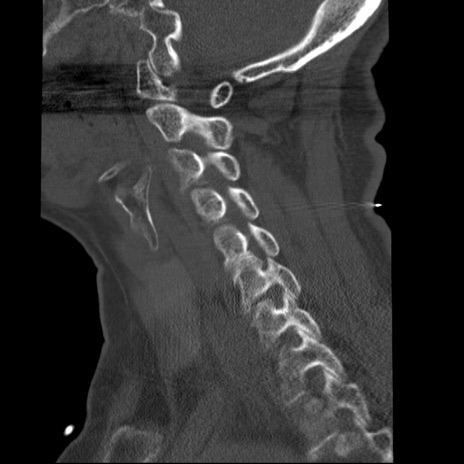

症例50 頚椎CT(矢状断像)

【症例】60歳代女性

【主訴】後頭部〜右後頸部にかけての痛み

【現病歴】本日飲食店でコーヒーを飲んでいたところ、突然後頭部〜右後頸部にかけて痛みが出現し、右上肢の感覚障害を伴ったため救急要請。

【身体所見】脳神経学的に明らかな異常所見を認めず。右上肢に軽度の感覚障害あり。

異常所見と診断は?

頚椎CT